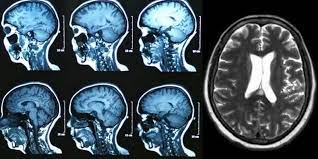

Brain Tumor Detection

Using deep learning techniques to detect brain tumors from medical images.